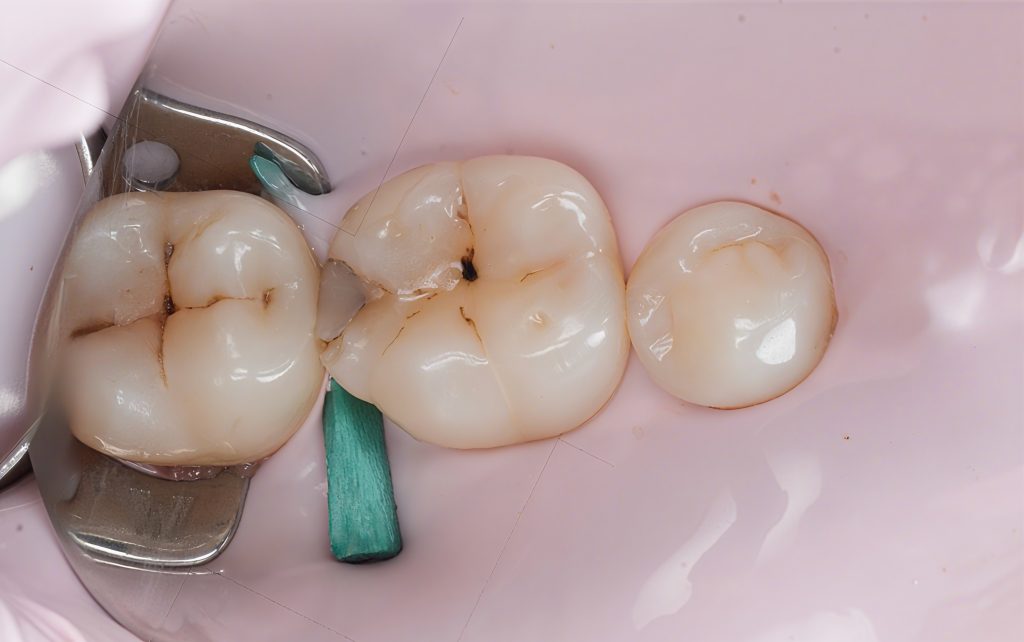

The patient presented with food impaction and discomfort around the distal surface of the mandibular first molar. Clinical inspection showed a defective contact and marginal staining. Radiographic evaluation confirmed a proximal carious lesion with no pulpal involvement. The objective was simple:

- Tooth: Mandibular first molar

- Primary issue: Proximal caries with lost contact

- Symptoms: Food packing, dull discomfort during chewing

Final Diagnosis: Class II distal carious lesion with open contact.

The old stained fissures and proximal lesion were accessed minimally.

Dark, demineralized dentin was removed carefully with controlled speed burs. The deepest dentin was preserved following selective caries removal to avoid unnecessary pulp stress.

You can clearly see in the photos:

- clean peripheral enamel

- sound dentin base

- a defined proximal box ready for matrix placement